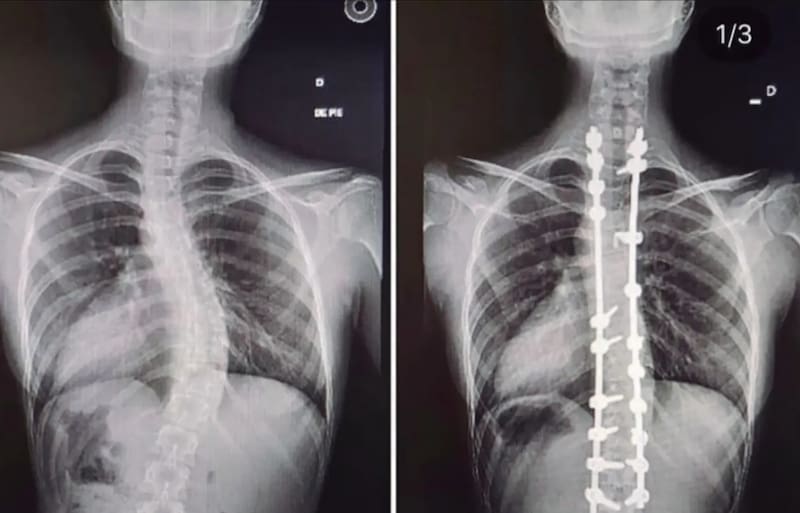

A temprana edad, los doctores le dijeron a la cientista política de 29 años que padece de escoliosis idiopática, es decir, encorvamiento en la columna vertebral. “No se sabe por qué pasó, porque no tuve un accidente, sino que en algún momento de mi vida se iba a manifestar, y me explicaron que teníamos que esperar que se cerrara el cartílago del crecimiento. Eso demora bastante, toda la adolescencia”, recordó en conversación con LUN.

Hace una década, cuando Fernanda Cornejo era una adolescente de 19 años, se sometió a la cirugía para tratar su diagnóstico. “Se fueron moviendo las costillas, las tenía muy adentro y eso tenía riesgo, por ejemplo, que se me perforara algún órgano, un pulmón, que apretara el corazón”, dijo al mismo medio, además de recalcar que ahora tiene “cuatro placas de titanio y, entre fierros largos, tornillos y clavos, tengo 68 (piezas) en la espalda”.